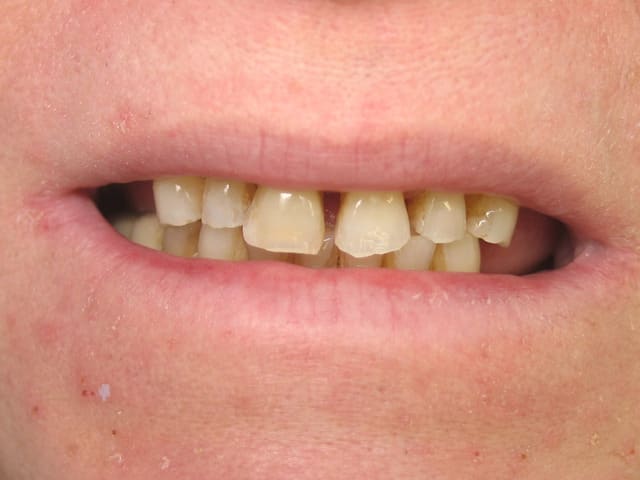

je refait actuellement les 4 incisives, le projet initial consistait à faire 4 dents

j'ai été un peu présomptueux sur mes capacités à conserver 11,

je doit me résoudre à l'extraire,

j’envisage de faire un bridge céramo céramique,

Vu la ligne du sourire, si le patient n'est pas demandeur et très motivé (pas de sourire gingival, pas de complexe par rapport à sa gencive), ne t'embête pas.

A priori pas de calage postérieur (cf. photo)?

Ton bridge CCC il va te l’exploser..... Déjà un bridge CCM je serai pas très confiant.